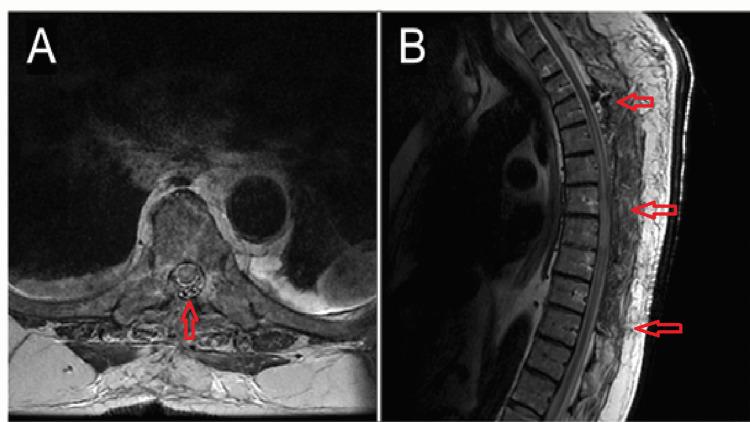

Spinal epidural lipomatosis (SEL) is a common pathology of the lumbar spine. While the natural history is not well understood, there is a strong association with metabolic syndrome and endocrine dysfunction. Clinical presentation typically involves slow, progressive onset of radicular and myelopathic symptoms. Treatment primarily consists of weight loss, while surgery is reserved for refractory cases or acute cauda equina syndrome. We present a case of acute spinal cord injury (SCI) after trauma with underlying SEL in the cervicothoracic spine. Additionally, a literature review using a MEDLINE search of the English literature through April 2020 following the Preferred Reporting Items for Systematic Reviews and Meta-Analyses (PRISMA) guidelines was performed to identify all documented cases of acute spinal cord injury with underlying SEL. A 72-year-old obese male with insulin-dependent diabetes mellitus presented with subacute bilateral lower extremity weakness after a fall with a flank injury three days prior to evaluation. Within hours of admission, the patient acutely progressed to paraplegia and sensory loss below the T6 level consistent with an ASIA (American Spinal Injury Association) A spinal cord injury. No fracture or dislocation was identified on CT imaging. MRI of the thoracic spine revealed spinal cord compression secondary to extensive posterior epidural lipomatosis with resultant anterior displacement of the thecal sac. The patient underwent emergent T2-T9 laminectomy for decompression. Post-operatively, the patient regained sensation below the level of injury. A review of the literature reviewed no published articles on cases of complete spinal cord injury secondary to underlying SEL without associated fracture. Finally, we present the first report of an acute spinal cord injury in the setting of SEL without fracture. Our case demonstrates that SEL outside the lumbar spine confers increased risk for SCI following trauma. Patients with cervicothoracic SEL may require close neurological observation and timely surgical decompression.

脊髓硬膜外脂肪增多症(SEL)是腰椎的一种常见病变。虽然其自然病史尚不完全清楚,但与代谢综合征和内分泌功能障碍密切相关。临床表现通常包括神经根性和脊髓病症状的缓慢、渐进性发作。治疗主要包括减重,而手术仅适用于难治性病例或急性马尾综合征。我们报告一例创伤后急性脊髓损伤(SCI)病例,其颈椎胸椎存在潜在的SEL。此外,按照系统评价和Meta分析的首选报告项目(PRISMA)指南,通过检索截至2020年4月的英文文献数据库MEDLINE进行文献综述,以确定所有记录在案的伴有潜在SEL的急性脊髓损伤病例。一名72岁的肥胖男性,患有胰岛素依赖型糖尿病,在评估前三天摔倒并伴有侧腹损伤后,出现亚急性双侧下肢无力。入院数小时内,患者迅速发展为截瘫,T6水平以下感觉丧失,符合美国脊髓损伤协会(ASIA)A级脊髓损伤。CT成像未发现骨折或脱位。胸椎MRI显示广泛的硬膜外脂肪增多症导致脊髓受压,继而硬脊膜囊向前移位。患者接受了急诊T2 - T9椎板切除术以减压。术后,患者在损伤平面以下恢复了感觉。文献综述未发现关于无相关骨折的潜在SEL继发完全性脊髓损伤病例的已发表文章。最后,我们报告了首例无骨折的SEL情况下急性脊髓损伤的病例。我们的病例表明,腰椎以外的SEL会增加创伤后SCI的风险。患有颈椎胸椎SEL的患者可能需要密切的神经学观察和及时的手术减压。